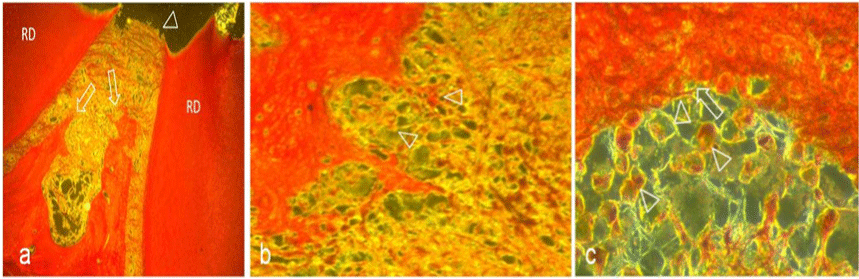

| Figure 1: Representative sections obtained from furcal perforation sites repaired with Geristore (a-c). a. Masson trichrom-stained section showing no reparative hard tissue apposition (open arrowhead) over the furcation site and severe interradicular bone resorption (open arrow). RD: radicular dentin. (Original magnifications 30X). b. Section from another specimen showing multinucleated osteoclast cells (open arrowhead) and inflammatory cells infiltrate separated by a tunnel defect (open arrowhead). (Original magnification 40X). c. Modified trichrome-stained section showing multinucleated osteoclast cells (open arrowhead) and resorptive lacunae (open arrow). |